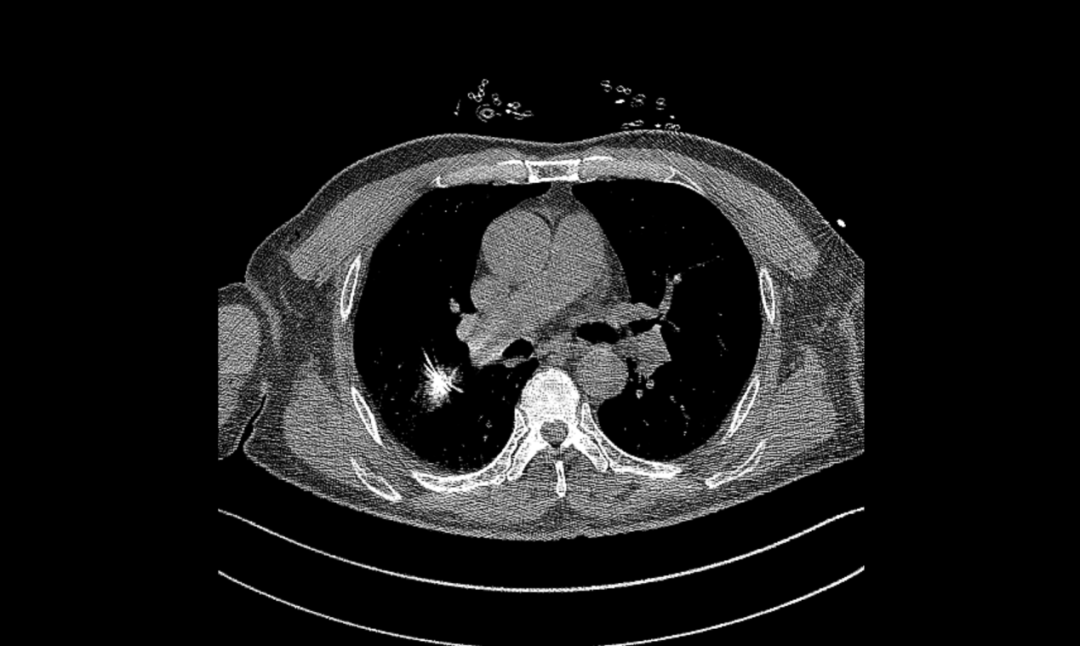

▲时丰主任带领团队行微波消融术

在罗少华主任统筹下,省医派驻专家时丰主任带领呼吸介入团队于5月28日为患者成功实施了微波消融术。手术过程中,我们密切监测患者的生理参数,确保治疗的安全性。经过精心治疗与护理,患者已顺利出院,目前病情稳定,恢复状况良好。

▲术中微波消融